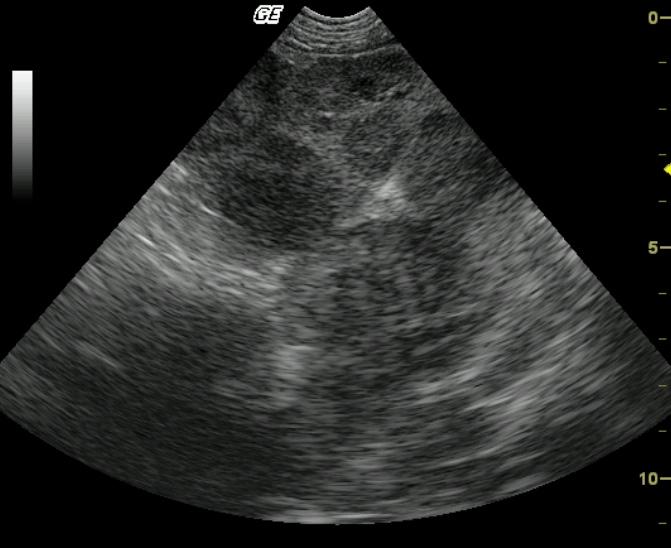

Coarse architecture is noted in both the spleen and liver with irregular capsular contour, echogenic and irregular tissue striations with nodular changes. This universal deviation from parenchymal architecture in both organs suggests a neoplastic process in both liver and spleen. The linear echogenic focus in the near field is a core biopsy needle.

Infiltrative and sclerosing splenic and hepatic pathology, likely neoplastic. Minor potential for aggressive inflammatory disease.

Fibrosarcoma, liver and spleen

Ultrasound guided FNAs of the liver and spleen were non-diagnostic. Ultrasound guided Tru-cut® biopsies of both liver and spleen revealed fibrosarcoma of the liver and spleen.